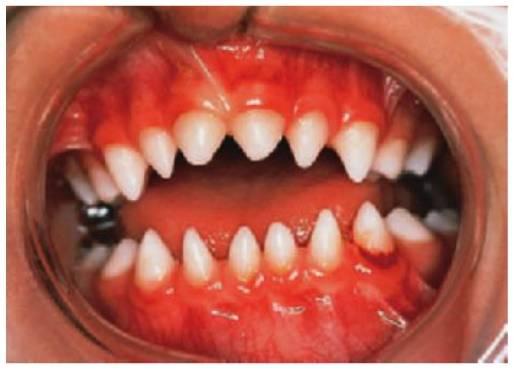

En algunos pacientes afectados por amelogénesis imperfecta, los dientes no llegan a erupcionar, se cree que debido a una alteración del órgano del esmalte y sufren una reabsorción de sus coronas. En algunos casos (más del 50%) se observa una mordida abierta esquelética anterior.

Formas predominantes/exclusivas de la hipoplasia dental

- Esmalte fino.

- Ausencia de punto de contacto entre los dientes.

- El esmalte puede ser rugoso, liso o con pozos repartidos al azar.

- Las mujeres heterocigóticas con amelogénesis imperfecta ligada al cromosoma X manifiestan lyonización (v. antes) con franjas verticales de esmalte normal y anómalo.

- La erupción de los dientes se retrasa.

- Los dientes que no han erupcionado pueden reabsorberse.

- Mordida abierta anterior asociada en aproximadamente el 50% de los casos.

- La ortodoncia, y puede que la cirugía ortognática, para corregir la mordida abierta anterior en las formas hipoplásicas.